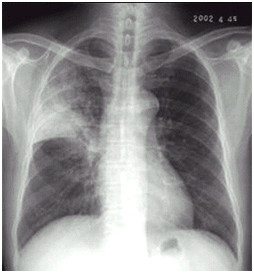

临床助理执业医师实践技能第一站【X线-胸腔积液】知识点模拟题

临床助理医师实践技能第一考站影像诊断模拟试题(2分)

临床执业助理医师实践技能第一考站【X线-肺癌】考点模拟题